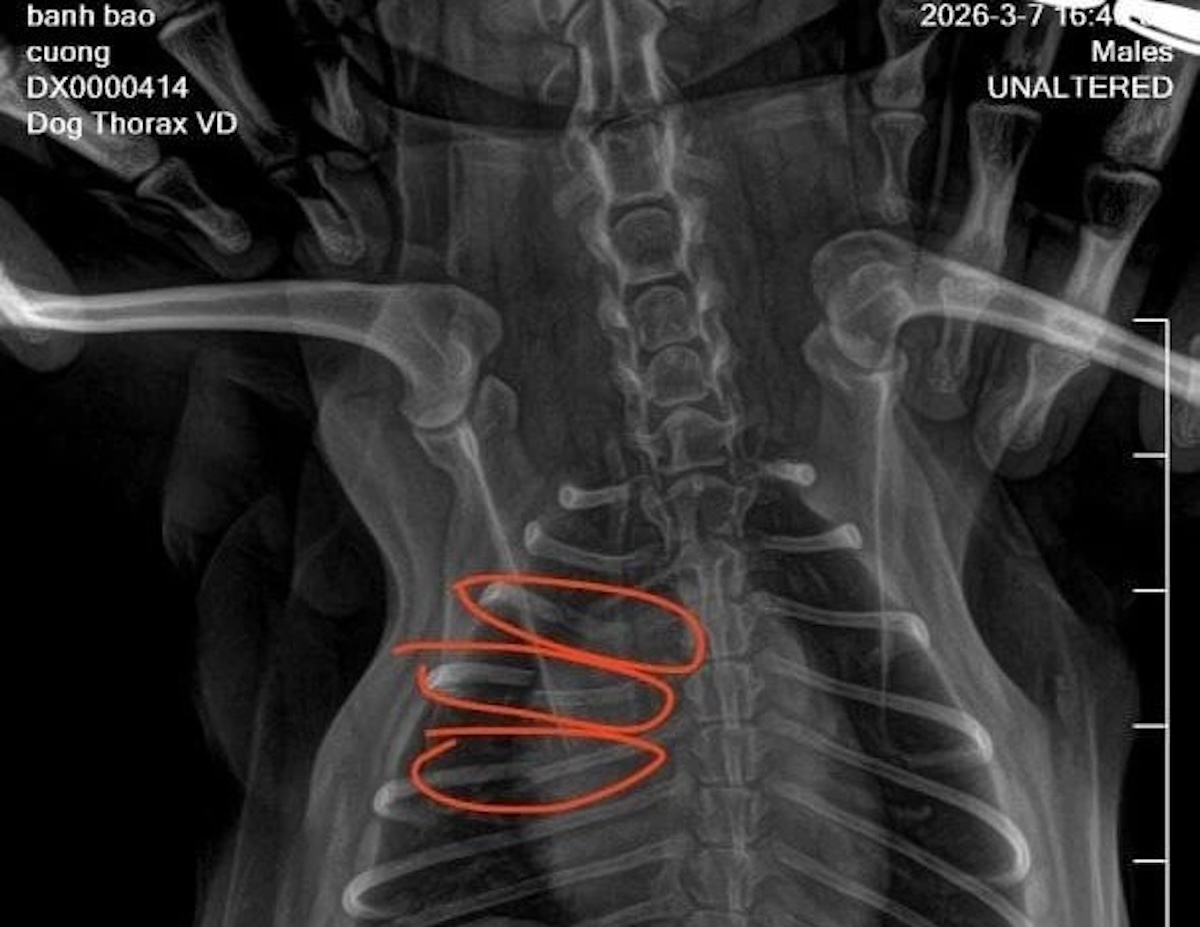

Kết quả chụp X-quang cho thấy chú chó bị gãy ba xương sườn. Do chú chó quá nhỏ nên bác sĩ bảo không thể bó bột được, chỉ đợi nó tự liền xương và phục hồi.